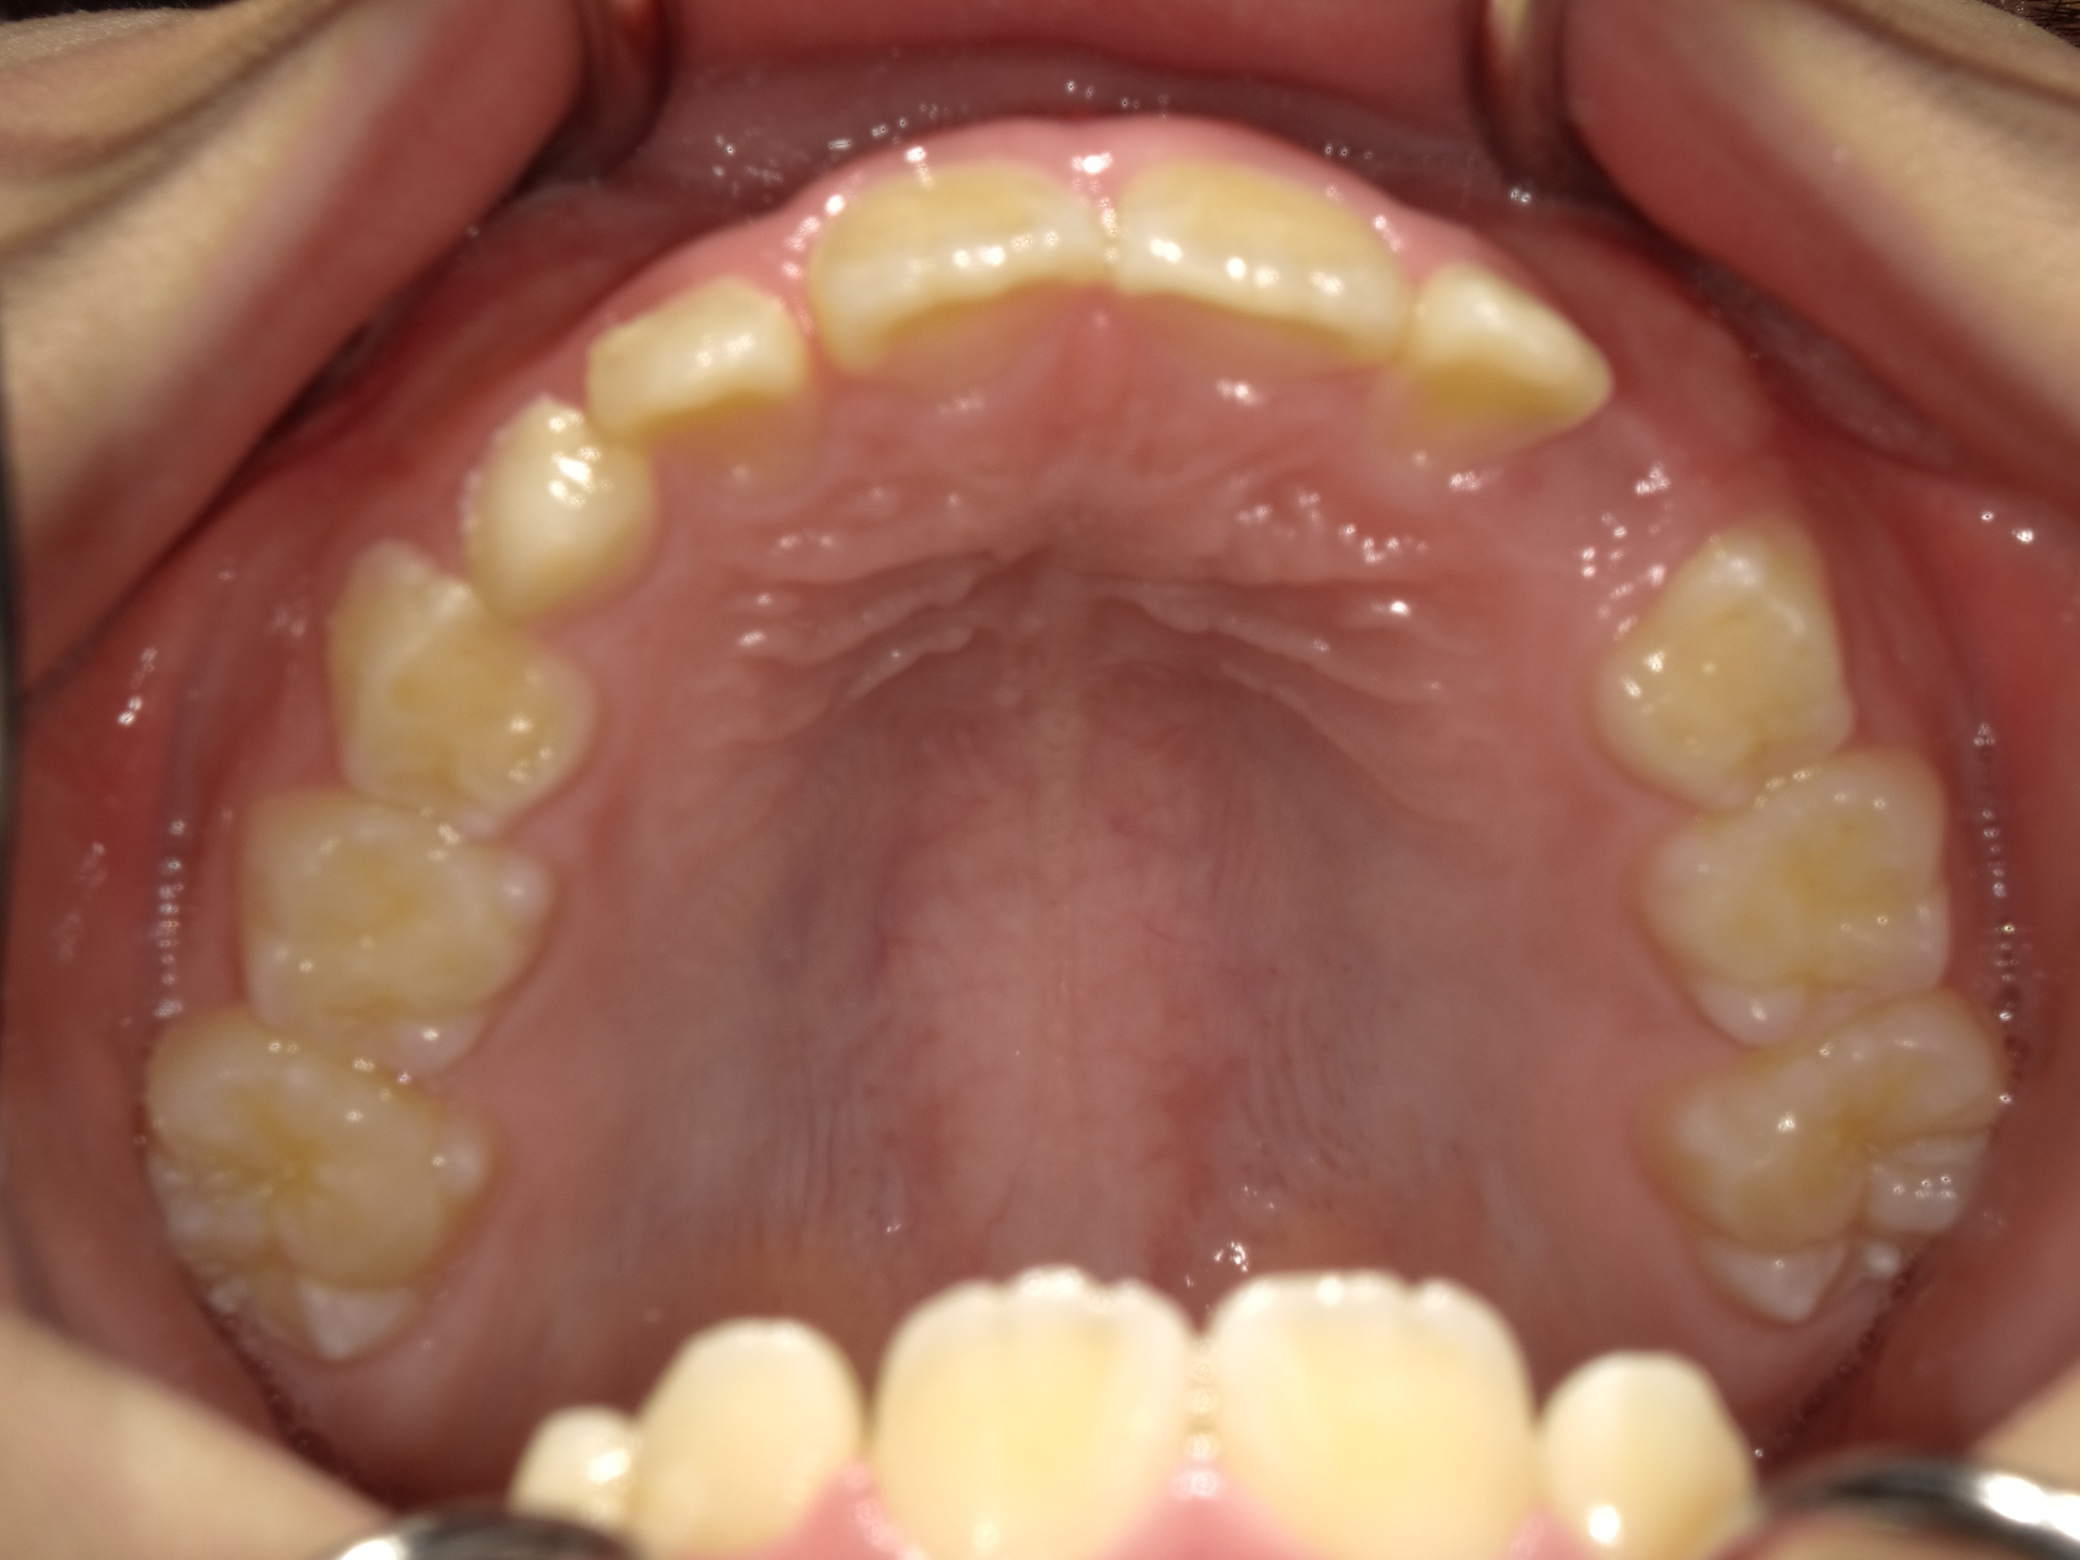

治療概要:黄色の丸の部分、まだ乳歯が抜けずに永久歯が内側から生えてきています。このままではこの乳歯は自然と抜ける可能性は低いので、まず、乳歯の抜歯を行いました。

治療前の状態

下の前歯も左右とも内側に生えている歯が並ぶスペースがなく、このままでは凸凹の状態が残ります。

また、横顔を見ても上唇が突出し、上顎前突(いわゆる出っ歯)の状態です。上の歯が下の歯を全て覆い前から見ても下の歯が見えません。

このままでは、将来的に奥歯の負担が大きくなり、歯を失う原因になる可能性があります。叢生(凸凹)の改善と、上顎前突の改善を目的に1期矯正を開始しました。

まずは拡大床という装置を使い、凸凹の改善を目指します。